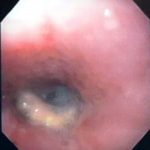

バリウム造影3時間経過するも、胃内からバリウム排泄なく同日内視鏡検査を実施。

内視鏡検査結果:内視鏡下にて、バスケット鉗子を用いて摘出。

症例は、机の上に置いていたピスタチオのお菓子を誤飲していました。その後の経過は良好です。本症例は、内視鏡下にて摘出ができましたが、球状・立体などの大きな異物は、腸の途中で詰まりやすく、内視鏡下での摘出が困難な場合もあります。その際は、開腹下にて腸内の異物を摘出しなくてはなりません。動物たちは、思わぬ物を誤飲することがあります。お留守番時・就寝時は、誤飲をしやすい時間帯ですので注意しましょう。